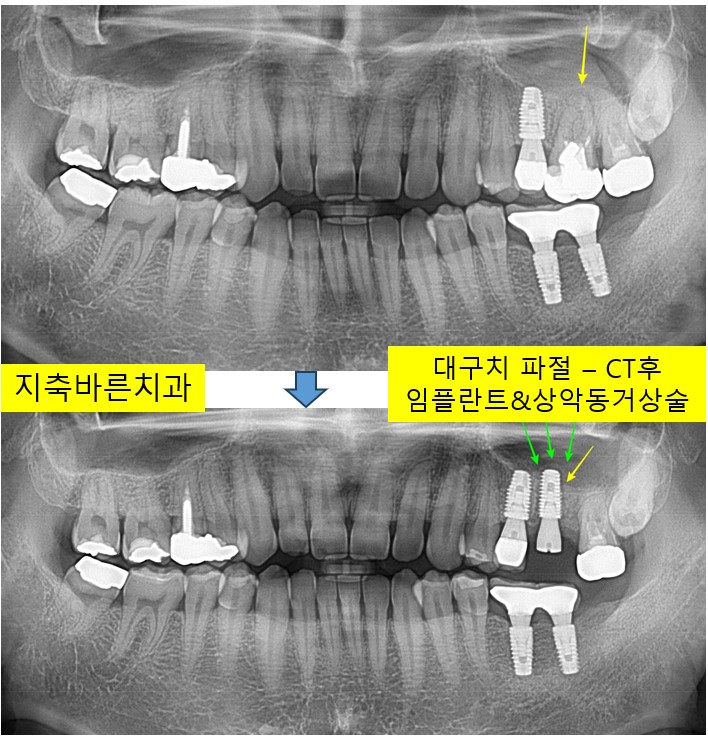

<왼쪽 위 제1대구치 뿌리 파절-CT판독 후 발치,GBR,임플란트>지축치과 지축역치과 삼송치과 원당치과 원흥치과 구파발치과 불광치과 은평치과 대화치과 종로치과 일산임플란트 미백4

전체검진과 스케일링을 하시러 2024년 5월 40대 Yㅁㅁ 님께서 내원해주셨습니다. 1. 처음 내원시 파노라마...